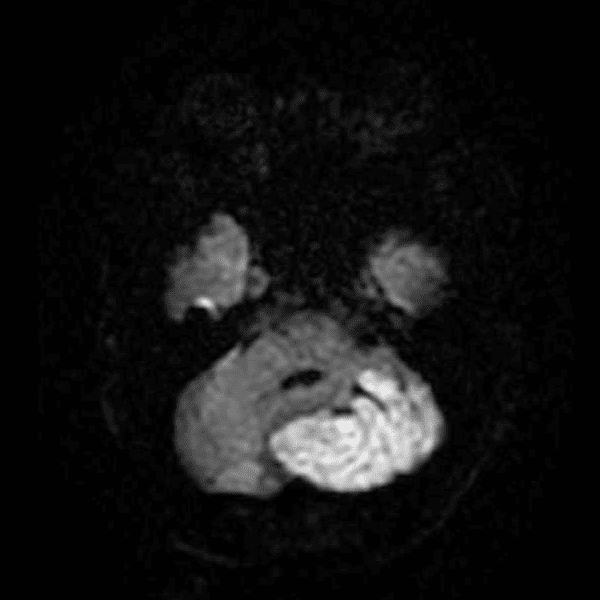

Classic Cases